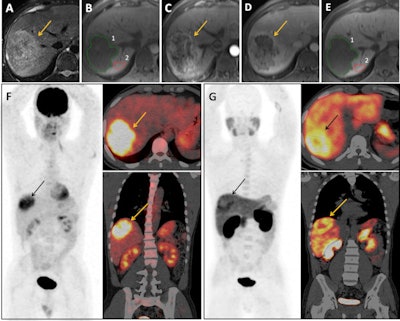

All patients underwent Gd-BOPTA-enhanced MRI including delayed HBP images, F-18 FDG PET/CT, and (for 29/32 patients) F-18 FCH PET/CT during the two months prior to surgery. For each lesion, the authors calculated the LLCER on MRI HBP images and the SUVmax tumor-to-liver ratio (SUVT/L) for both tracers. They analyzed and compared the predictive value for aggressive pathological features, including the histological grade and MVI, as well as the RFS.

The area under receiver operating characteristics for the identification of aggressive HCCs on pathology with LLCER, F-18 FDG SUVT/L, and F-18 FCH SUVT/L were 0.92 (95% confidence interval [CI] 0.78, 0.98), 0.89 (95% CI 0.74, 0.97; p = 0.70), and 0.64 (95% CI 0.45, 0.80; p = 0.035). LLCER was identified as an independent predictor of RFS (HR [95% CI] = 0.91 [0.84, 0.99], p = 0.022). LLCER − 4.72% or less also accurately predicted moderate to poor differentiation grade (sensitivity = 100%, specificity = 92.9%) and MVI (sensitivity = 93.3%, specificity = 60%) and identified patients with poor RFS after surgical resection (p = 0.030).

After surgical resection for HCC, patients with an LLCER of -4.72% or less had significantly poorer recurrence-free survival than patients with an LLCER superior to -4.72%, according to the authors.